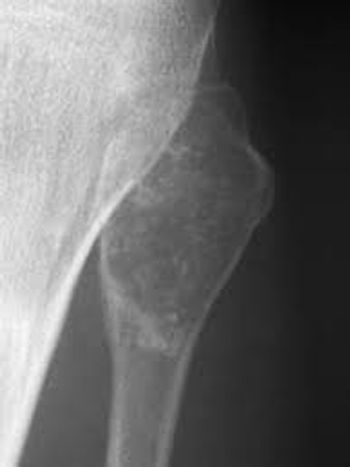

Among patients with chondrosarcomas, the most common primary bone tumor in adults, the presence of a TP53 gene mutation has been found to be associated with worse overall survival and metastasis-free survival.